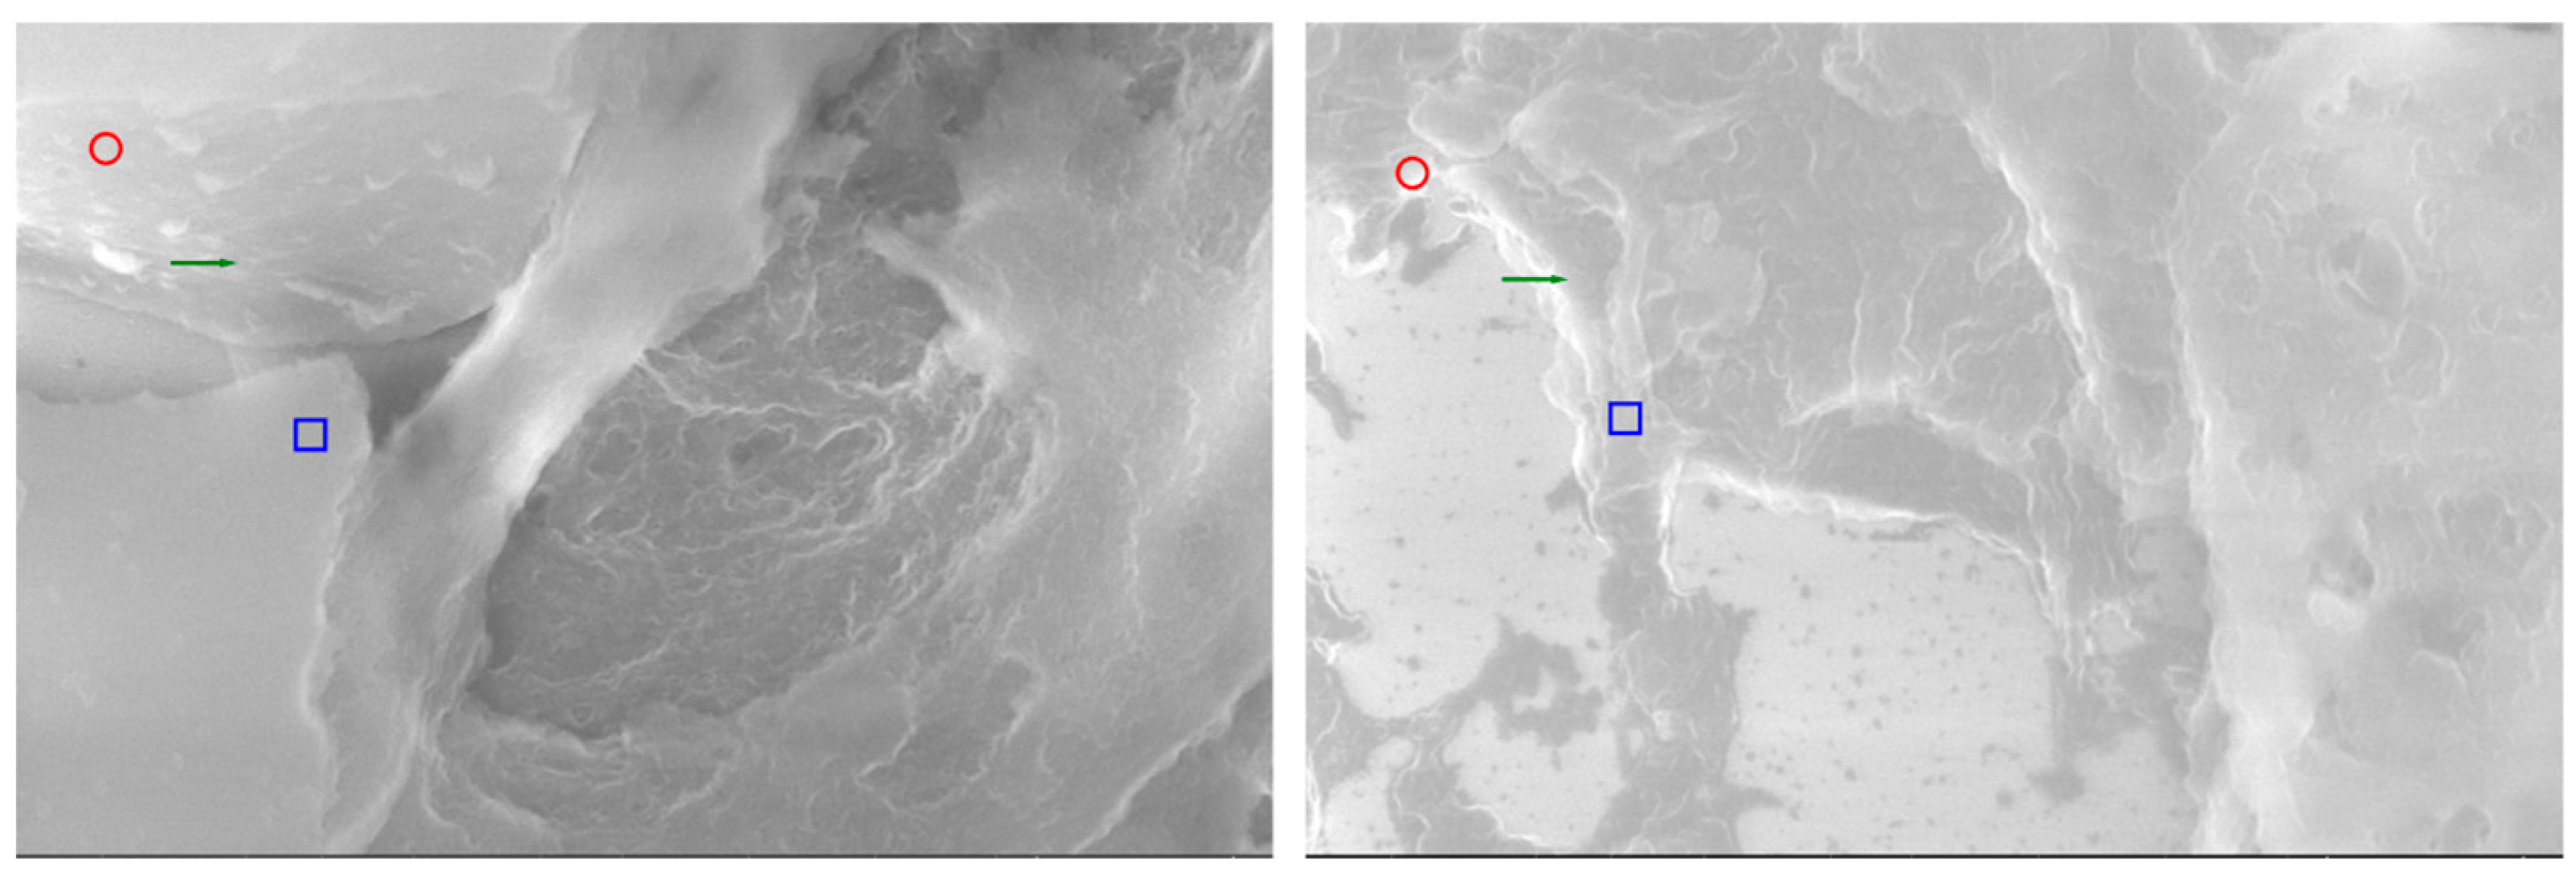

Comparative analysis by SEM at high magnification (20,000×) offers a unique perspective on the ultrastructural parallels between thymic and parathyroid tissues (Figure 7). Beyond their embryological proximity, the two glands reveal a series of morphological analogies that can only be appreciated at this resolution, where the tridimensional relief of the stromal framework and the fine surface specializations become evident. The present images illustrate side-by-side the thymus and the parathyroid gland, each annotated to highlight microvillous projections, vascular-like channels, and stromal condensations. Such features, although originating from histologically distinct organs, demonstrate convergent patterns of organization, suggesting that their functional interplay may be mediated not only by molecular cross-expression but also by shared ultrastructural substrates. By emphasizing these parallels, the comparative SEM approach strengthens the working hypothesis of a parathyroid–thymus possible portal system and provides visual evidence that bridges histological, immunohistochemical, and functional data into a coherent morpho-functional model.

Figure 7. SEM images of thymus ((left) 20,000×) and parathyroid ((right) 20,000×, enhanced). Red circles mark microvillous projections; green arrows indicate vascular-like grooves or intercellular clefts; blue rectangles highlight stromal condensations. Annotations emphasize ultrastructural similarities consistent with a possible functional parathyroid–thymus interconnection.